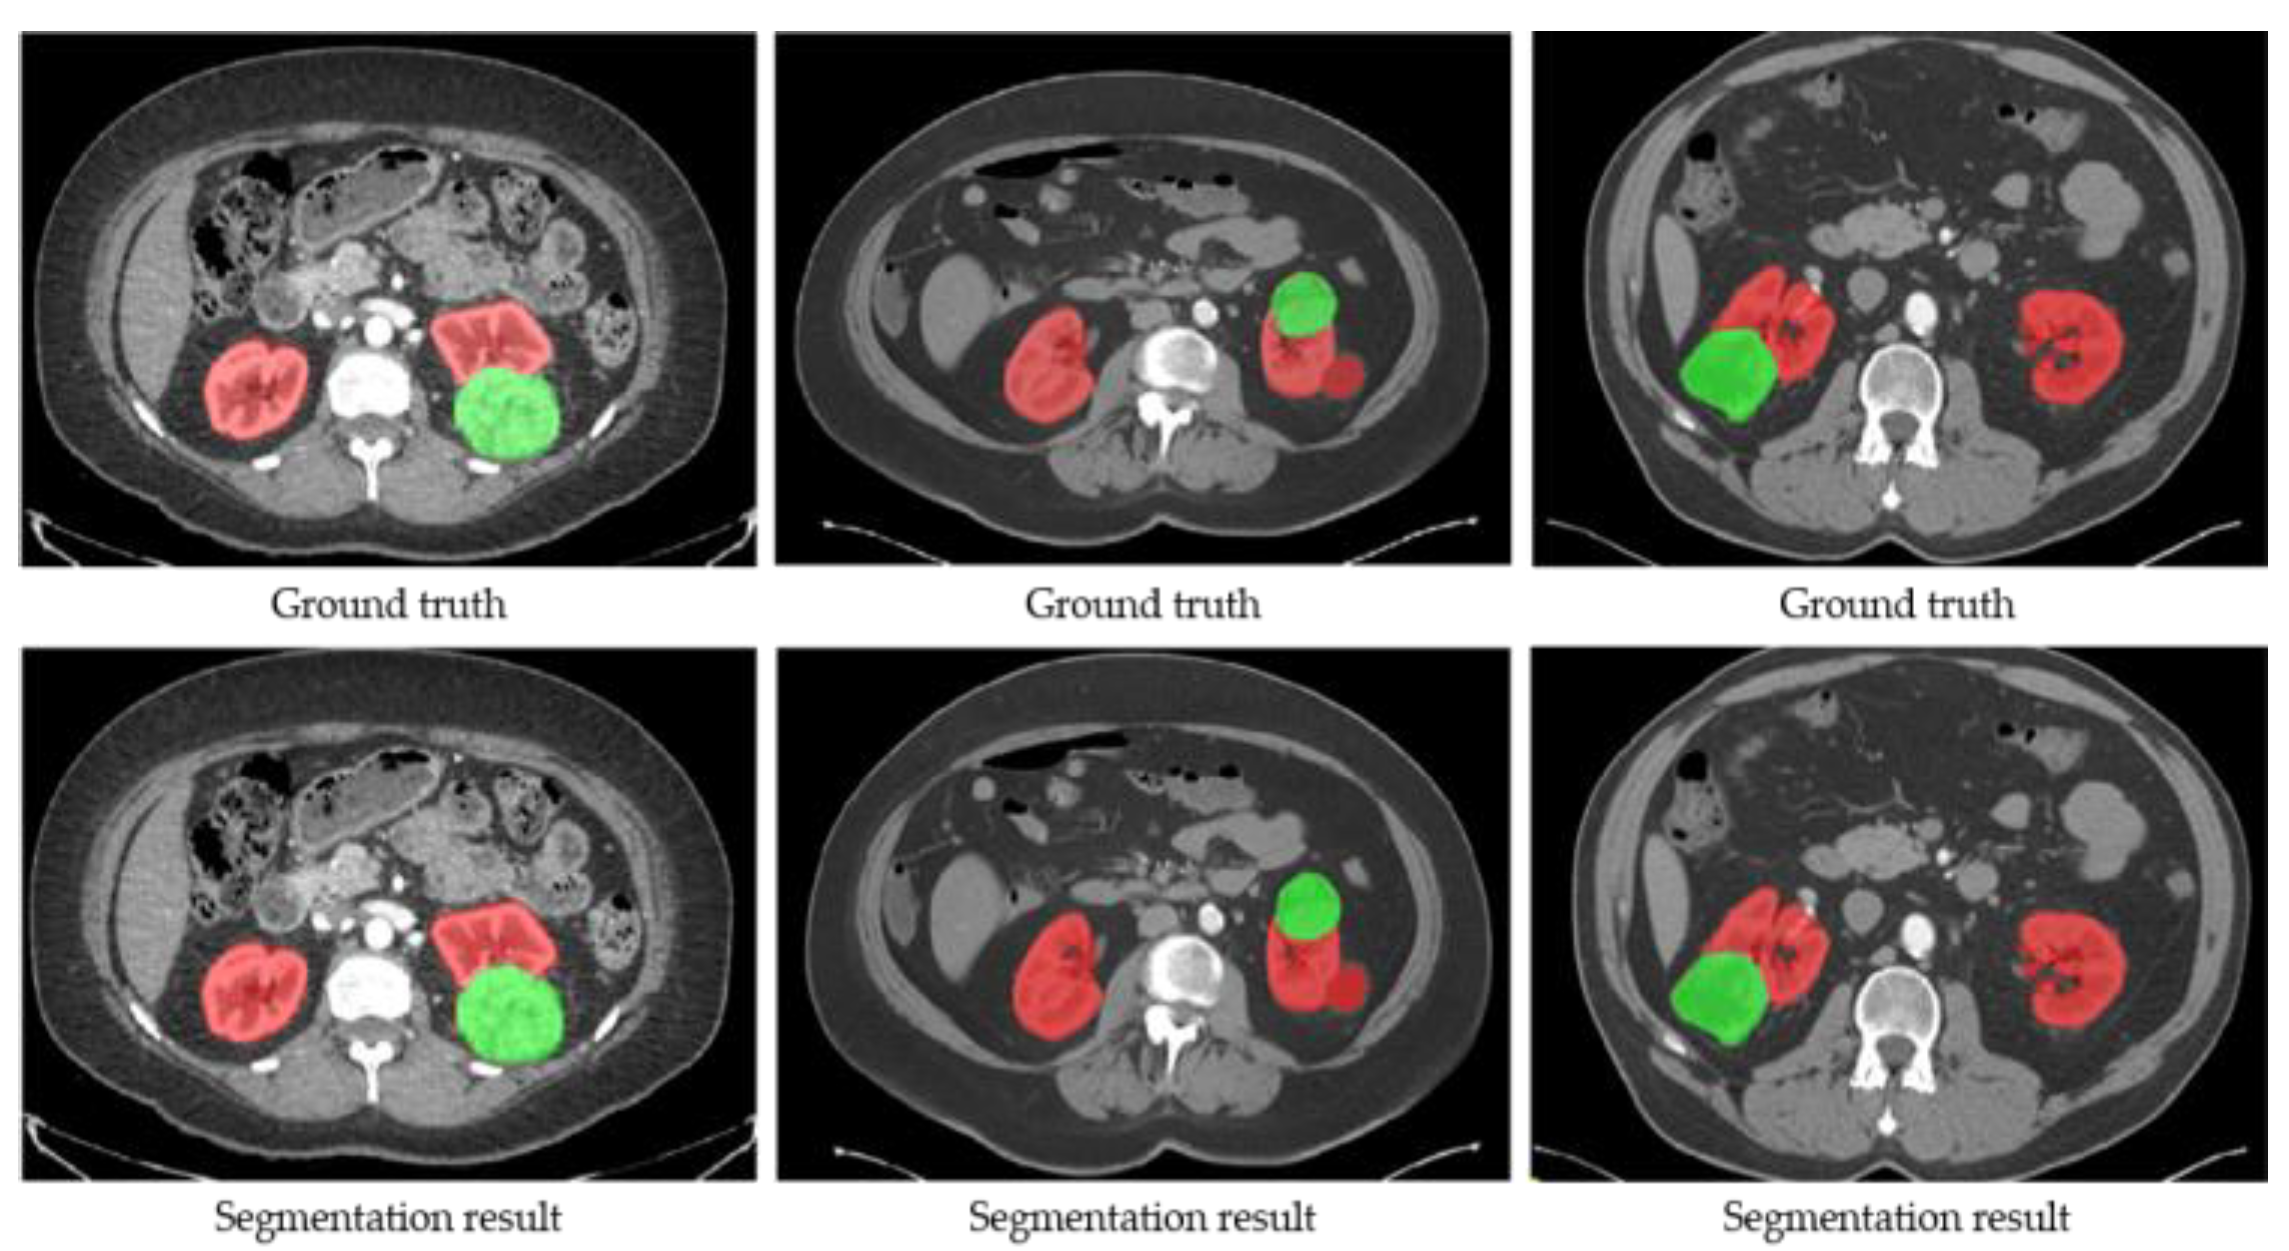

Firstly, the training and validation datasets are employed to update the weights and decide the optimal hyper-parameters of SegTGAN, respectively. Then, the performances of SegTGAN on the Kits19 and Kits21 testing datasets are measured. The ACC, DSC, and SEN of SegTGAN on the Kits19 and Kits21 datasets are 0.9728/0.9526/0.9539 and 0.9676/0.9507/0.9344, respectively. Some segmentation results of SegTGAN on Kits21 are shown in Figure 4.

Figure 4.

Examples of the segmentation results of SegTGAN on the Kits21 dataset. Red contour denotes the kidney and green contour denotes a tumor.